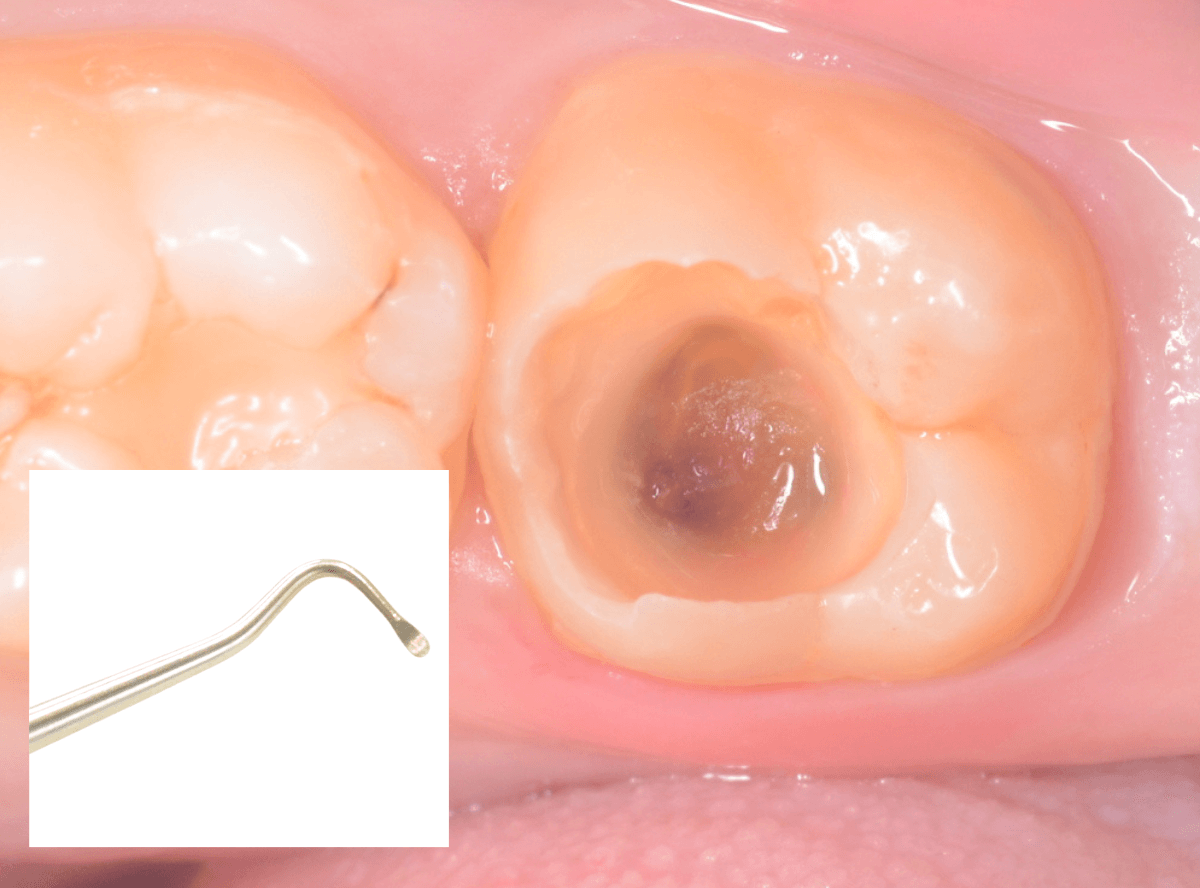

Case.14 インレーの下の歯肉まで広がった虫歯

「下の奥歯が噛むと痛む」という症状で来院された患者さんのケースです。

お口の中の状態を確認すると、奥歯の端に穴が開いているのが見えます。

ここかな?

レントゲン写真で確認します。

やはり、奥歯の端が大きな虫歯になっています。

青いラインが歯の神経、赤いラインが虫歯です。

レントゲン写真上では虫歯が神経まで達しているように見えます。

これは、神経を取らないとダメかもしれません。